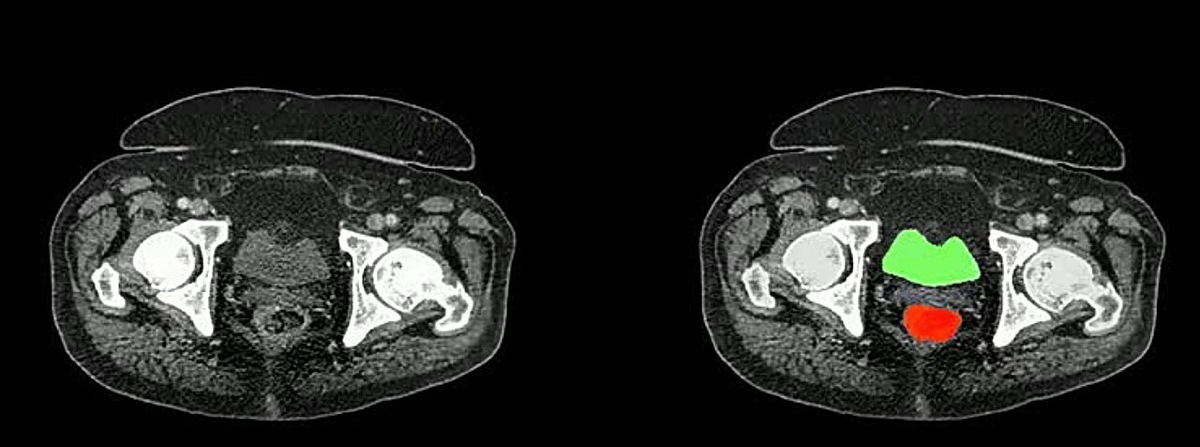

Международная группа ученых, возглавляемая исследователями из Университета Джонса Хопкинса, представила крупнейшую в мире базу данных компьютерных томографий брюшной полости — AbdomenAtlas. Этот проект, основанный на искусственном интеллекте, может значительно ускорить диагностику рака и других заболеваний. AbdomenAtlas включает более 45 000 трехмерных КТ-сканов из 145 больниц по всему миру и содержит аннотации к 142 анатомическим структурам. По масштабам он превосходит все существующие аналогичные базы данных более чем в 36 раз. Ранее разметка медицинских изображений требовала огромных затрат времени: вручную пометить 45 000 снимков с 6 миллионами анатомических структур у одного специалиста ушло бы более 2000 лет. Однако исследователи применили методику, сочетающую три ИИ-модели, которые анализируют снимки, прогнозируют аннотации и передают самые сложные участки на проверку радиологам. Такой подход позволил ускорить процесс разметки органов в 500 раз, а выявление опухолей — в 10 раз.

AbdomenAtlas включает более 45 000 трехмерных КТ-сканов из 145 больниц по всему миру и содержит аннотации к 142 анатомическим структурам. По масштабам он превосходит все существующие аналогичные базы данных более чем в 36 раз.

Ранее разметка медицинских изображений требовала огромных затрат времени: вручную пометить 45 000 снимков с 6 миллионами анатомических структур у одного специалиста ушло бы более 2000 лет. Однако исследователи применили методику, сочетающую три ИИ-модели, которые анализируют снимки, прогнозируют аннотации и передают самые сложные участки на проверку радиологам.

Такой подход позволил ускорить процесс разметки органов в 500 раз, а выявление опухолей — в 10 раз. В результате удалось создать наиболее точную и детализированную базу данных, которая уже используется для обучения новых ИИ-моделей, способных выявлять злокачественные образования и диагностировать заболевания на ранних стадиях.